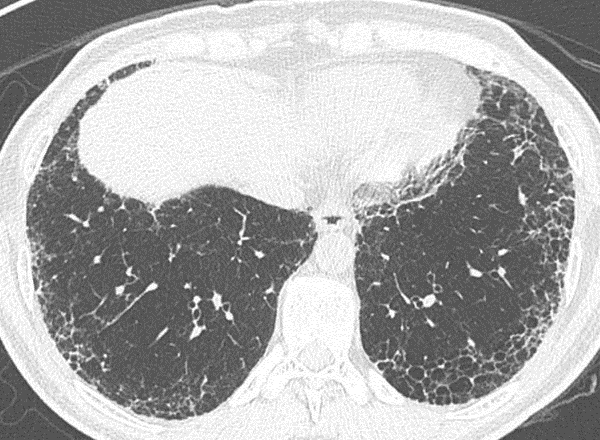

Figura 1A e B: Paciente com fibrose pulmonar idiopática mostrando franca progressão da doença nos exames de imagem de seguimento com diferença de 1 ano. Note a maior extensão do reticulado, bronquiectasias, bronquiolectasias e do faveolamento em B.